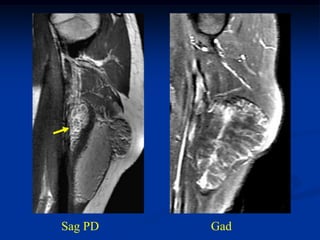

Case #295.1           Recurrent hemangioma

24 year female with recurrent hemangioma triceps

Coronal T-1   T-2

Sagittal T-1   T-2

Axial     T-2

T-1

Gad

Case #295.1 Recurrent hemangioma phleboliths 24 year female with recurrent hemangioma triceps

Axial T-2 T-1 Gad